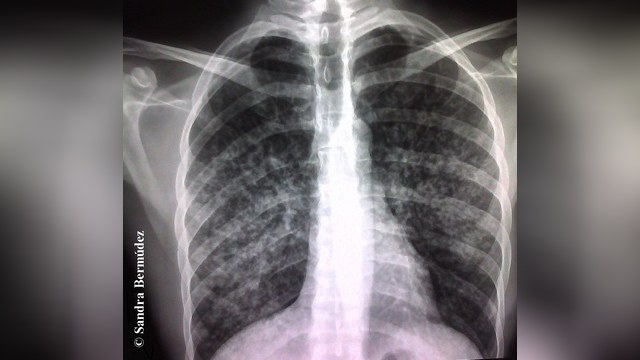

Le Figaro: русские, чеченцы и грузины заражают Францию туберкулезом